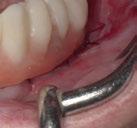

Ejecución técnica quirúrgica mediante férula guiada Bajo anestesia infiltrativa realizamos extracciones atraumáticas de todas las piezas a excepción de los dientes que actúan como anclaje o pilares para la fijación de la férula quirúrgica (Figuras 20 y 21). Seguidamente insertamos la férula comprobando una buena adaptabilidad y estabilidad

Figura Figura en posición ideal. Figura Figura

Figura

de dientes estratégicos para fijar la férula quirúrgica.

Figura 23. Férula quirúrgica inferior. Figura 24. Fresado guiado con férula y cucharilla. Figura 20. Extracciones dentales. 21. Conservación Figura 22. Férula quirúrgica superior. Figura 25. Inserción de implante RSX de Bego a través de férula quirúrgica. Figura 27. Conexión de pilar angulado multiplus sobre implante. Figura 26. Implante insertado en lecho a través de férula quirúrgica. Figura 28. Muestra del perfecto paralelismo tras la colocación de pilares angulados multiplus. Figura 29. ScanBody sobre pilares transepiteliales.